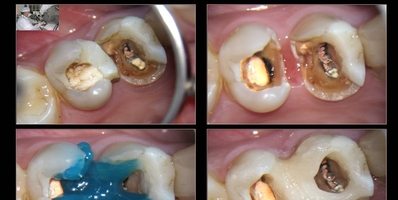

Todo dente indicado para tratamento endodôntico deve passar por uma avaliação e tratamento prévio da estrutura radicular, promovendo um reforço coronário, com levantamento de paredes perdidas, em resina composta, para facilitar tanto o isolamento absoluto quanto evitar possíveis fraturas durante o próprio tratamento, quando em sessões múltiplas, ou após a terapia endodôntica, devido à fragilidade do remanescente frente aos esforços mastigatórios. Uma boa avaliação prévia pode definir o futuro do elemento dental. Pois, de nada adianta um eficiente tratamento endodôntico se o dente encontra-se fragilizado. O reforço prévio da coroa  juntamente com o selamento coronário e uma restauração pós-endodôntica adequada são pré-requitos fundamentais quanto à preservação da unidade dentária.

Este tratamento prévio tem início com uma inspeção minuciosa em toda estrutura corono-radicular, periodonto e observação de possíveis micro-trincas em uma das paredes, nódulos pulpares, cáries sub-gengivais, etc…

Protocolo de execução do reforço coronário com resina composta:

1- Remoção total da cárie (se existir), regularização de paredes laterais com eliminação das partes comprometidas.

2- Ataque ácido (ácido fosfórico 35%) por 30s, seguido de irrigação com água destilada ou soro fisiológico

3- Secagem sem exagero e aplicação do adesivo dentinário

4- Levantamento das paredes laterais com resina fotopolimerizável